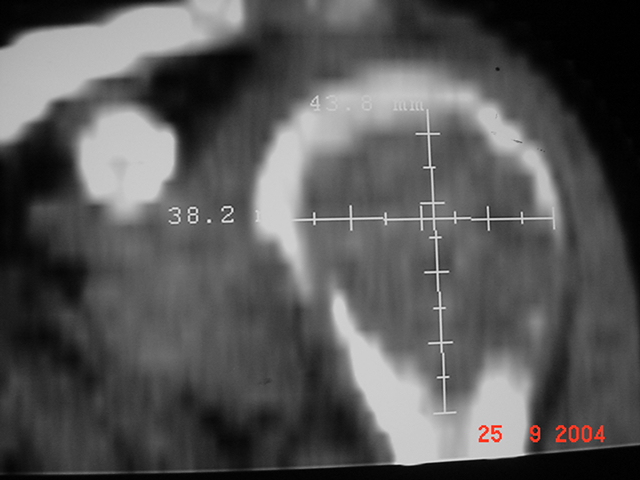

RX SIMPLE TAC |